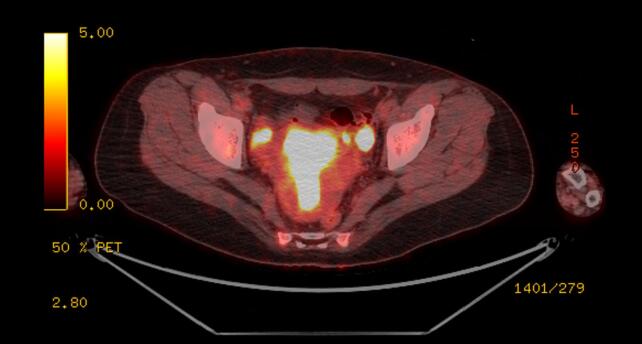

Given the severity and change in quality of the headaches, brain magnetic resonance imaging (MRI) was obtained, which showed multiple rim-enhancing lesions associated with vasogenic edema (Fig. 1). She was admitted to the neurology service. Her physical and neurologic exams were normal. Cerebrospinal fluid (CSF) studies did not reveal a lymphocytic pleocytosis, and cultures for bacteria, mycobacteria, and fungi were negative. CSF pathology was negative for malignancy. MRI of the spine demonstrated abnormal T2 signals at C4 and T10, concerning for metastatic lesions. Computed tomography (CT) of the chest, abdomen and pelvis revealed a 0.5 mm right upper lobe ground-glass pulmonary nodule, left fallopian tube dilation concerning for salpingitis, and an attenuating 1.6 cm structure in the right adnexa (Fig. 2). The patient underwent positron emission tomography (PET/CT), which showed intense heterogenous hypermetabolic activity in the endometrium, cervix, and left external iliac nodes, with thickened left fallopian tube showing intense metabolic uptake (Fig. 3). The previously observed right adnexal mass had no uptake and was felt to be non-specific. The reported T10 spinal lesion was also metabolically active.

Fig. 3.

PET-CT: Thickened left fallopian tube and endometrium,with intense uptake.